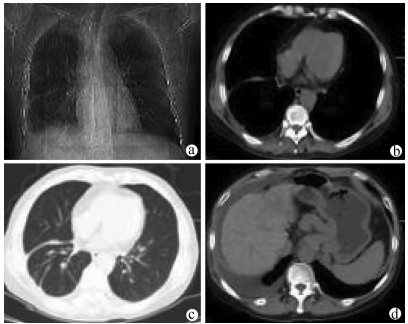

胸膜腔内注射聚桂醇治疗难治性肝性胸水1例报告

李常洲, 李建辉, 郝欣, 姜海斌, 王爱民, 花海洋, 齐静, 张静哲

2021, 37(9): 2177-2179. DOI: 10.3969/j.issn.1001-5256.2021.09.033

摘要(823) HTML (236) PDF (2488KB)(50)

摘要: